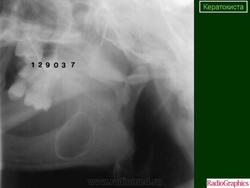

Одонтогенная кератокиста. Одонтогенная кератокистаобразуется из остатков зубной пластинки и диагностируется на основании гистологического исследования. Она представляет собой первичную (примордиальную) кисту, образующуюся при нарушении развития зуба (например, третьего моляра). Кисту обычно выявляют на втором или третьем десятилетии жизни, чаще у мужчин. Больные нередко не предъявляют жалоб. На рентгенограммах киста может быть однокамерной, но чаще она многокамерная. Края кисты чётко очерчены, фестончаты; могут быть признаки деструкции кости. В самой кисте заметны перегородки, а наличие в ней роговых масс обусловливает гомогенный дымчатый фон полости. При гистологическом исследовании эпителий кисты однороден, состоит из 8—10 слоев клеток с выраженными признаками ороговения. К концу 10-го года после иссечения одонтогенной кератокисты рецидивы отмечают у 50% больных.